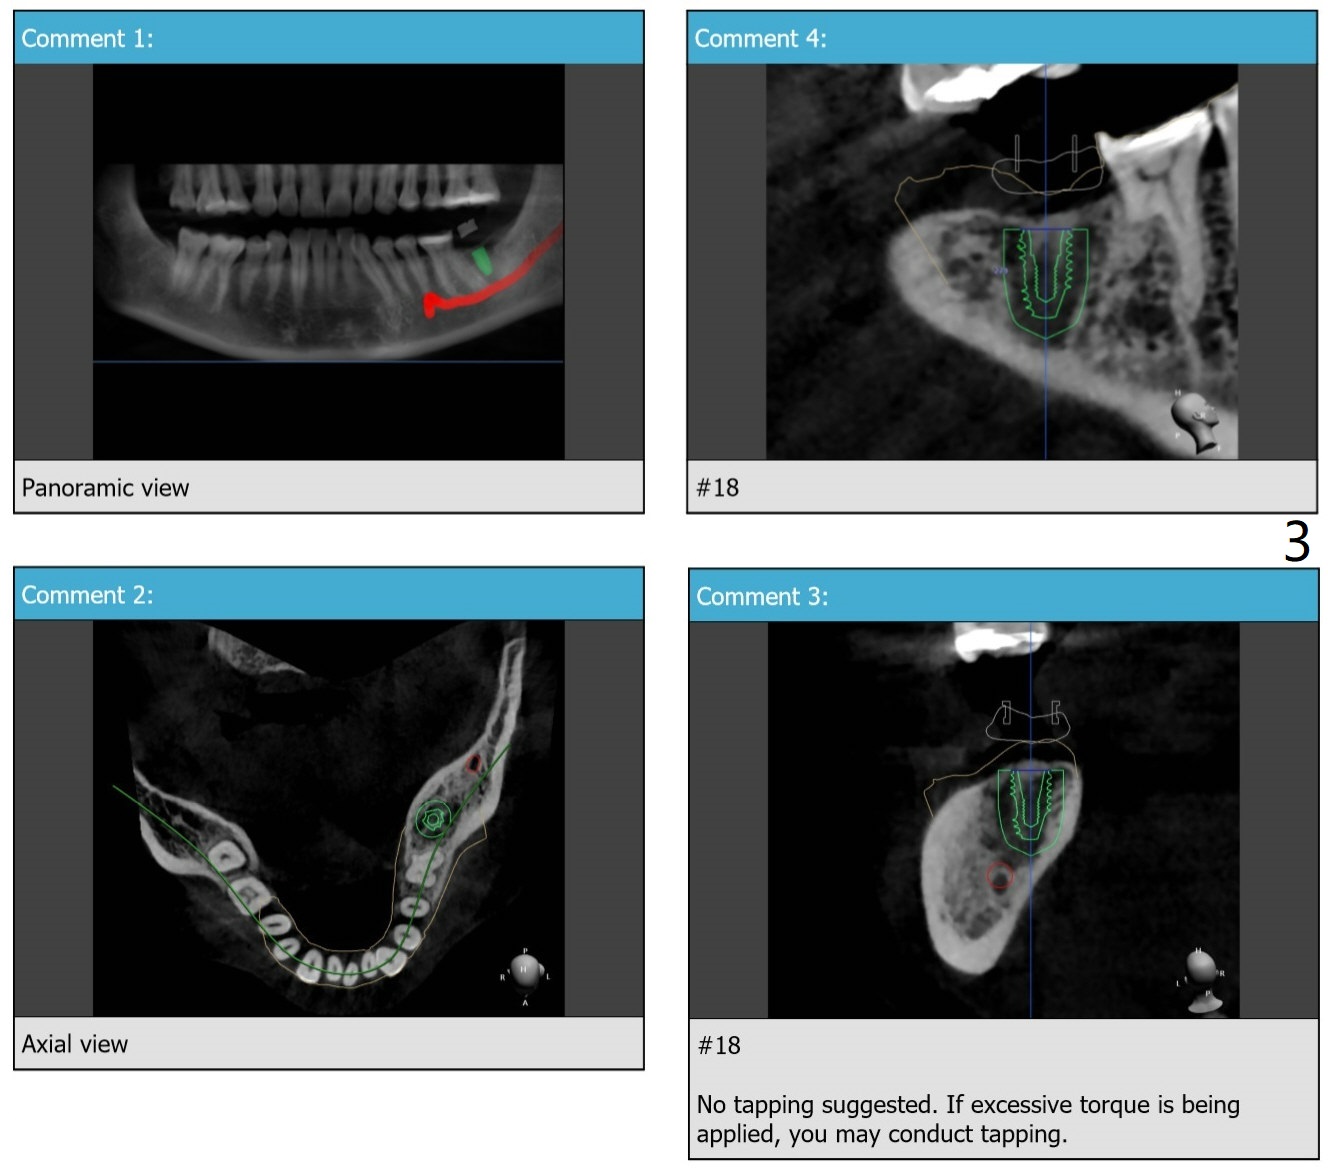

Limited Mouth Opening

Before surgery, measure the interincisal edge distance. It should be 45 mm to have smooth surgery. Call the patient whether she has taken measures to reduce the trismus (night guard and muscle relaxant).